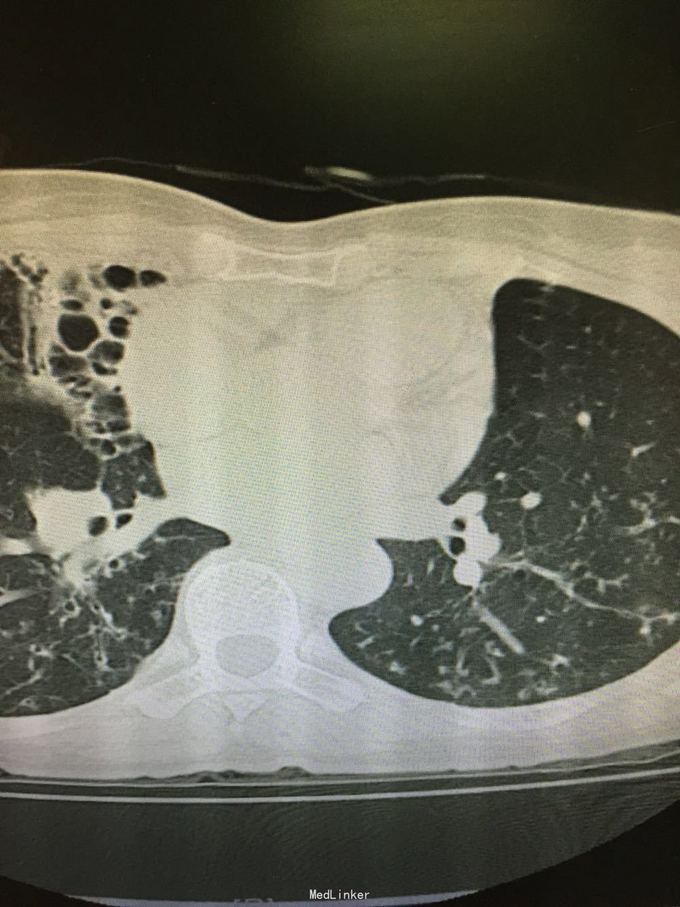

63岁女性,因“反复咳嗽、咳痰5年,加重1年”入院。

查体:双肺呼吸音粗,双上肺可闻及哮鸣音,双下肺可闻及干湿性罗音。外院胸片示两上中肺可见片装阴影,密度不均匀,边缘模糊,左中肺病灶中可见一椭圆形透光区,大小1.5*2.0cm;双肺纹理增粗、紊乱。考虑继发性肺结核(III上/上中。进展)我院胸片考虑支气管扩张。

诊断:支气管扩张并感染;肺结核?。入院后予甲磺酸左氧氟沙星200mlQd静滴治疗。

肺结核患者易并发支气管扩张。该患者影像学表现为碎饼干渣样,为较典型结核播散灶。支气管扩张表现也较典型。